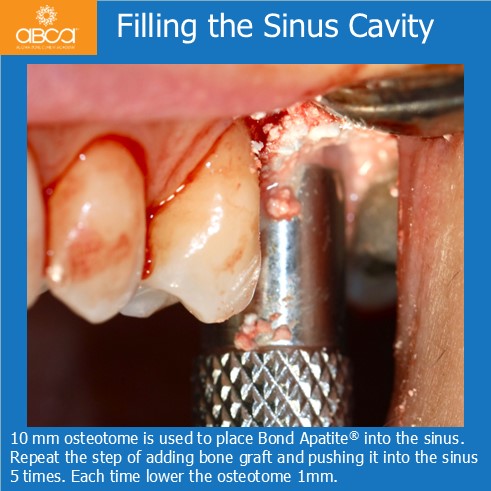

Sinus lift with Augma Lift™ Kit B with 4-5 mm sub sinus bone height.

Sinus lift with Augma Lift™ Kit B with 4-5 mm sub sinus bone height. A young woman came to replace the missing first maxillary molar with moderate atrophy.

Sinus lift with Augma Lift™ Kit B in a case with 5 mm sub sinus bone height.

Sinus lift with Augma Lift™ Kit B in a case with 5 mm sub sinus bone height. The patient came for implant treatment in the region of teeth #16 (3)…